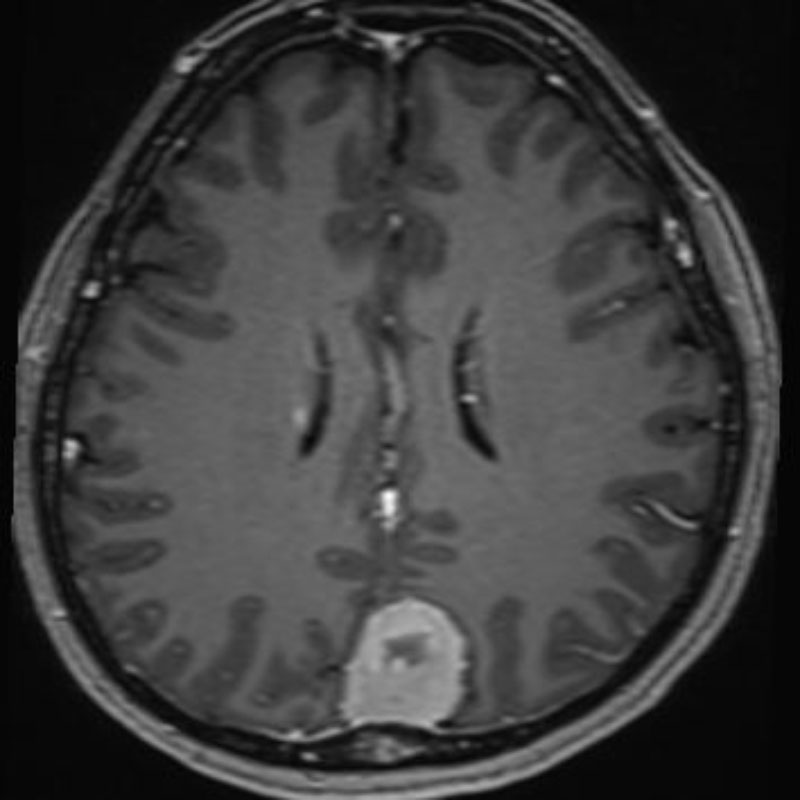

624

'25年4月

70代

後頭葉膠芽腫

頭蓋内腫瘍摘出術

No.’25_26 手術前1

No.’25_26 手術前2

No.’25_26 摘出 前

No.’25_26  摘出 中

No.’25_26 摘出 後